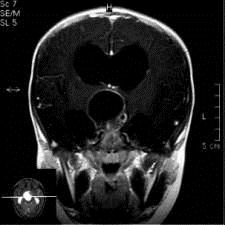

问题 病历摘要:??患者女性,6岁,半年来感觉视力模糊,近10天出现反复头痛,间有恶心呕吐,精神转差,查体:神志清楚,身高90cm,体重25Kg,血压90/55mmHg,右眼视力4.6,左眼视力4.8,双侧视乳头水肿,颈软,伸舌居中,四肢肌张力正常,肌力5级,双侧Babinski征(-)。 患者术后第一天,神志嗜睡,精神疲倦,皮肤干燥,38.2℃,心率155次/分,Bp102/60mmHg,中心静脉压3mmHO,Na160mmol/L,尿量很多,色清如水,应作的处理措施有?